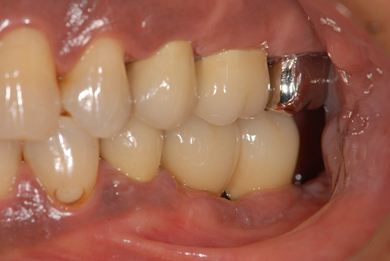

インプラントの症例写真 IMPLANT

インプラント治療+セラミック治療

| 治療内容 | インプラント2本、メタルボンドセラミッククラウン7本(メタルボンド用土台5本)、歯肉歯槽骨整形手術 | ||||||||||||||||||||||||||||||||

| 治療期間 | 11ヶ月 |